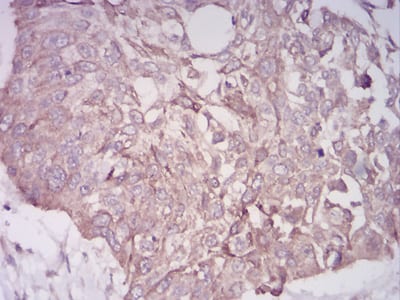

分类: 科研抗体货号: 30876别名: APR; LRP; A2MR; CD91; APOER; LRP1A; TGFBR5; IGFBP3R应用: IHC,IF反应种属: Human

分类: 科研抗体货号: 30875别名: OP-1应用: WB,IHC,FCM反应种属: Human,Mouse